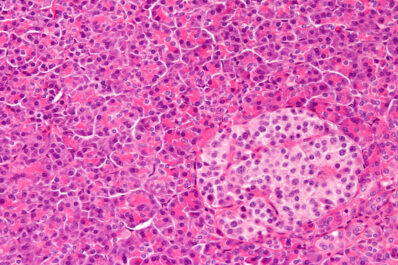

The lab of Kathy DelGiorno, assistant professor of cell and developmental biology, seeks to understand changes in the pancreas in...